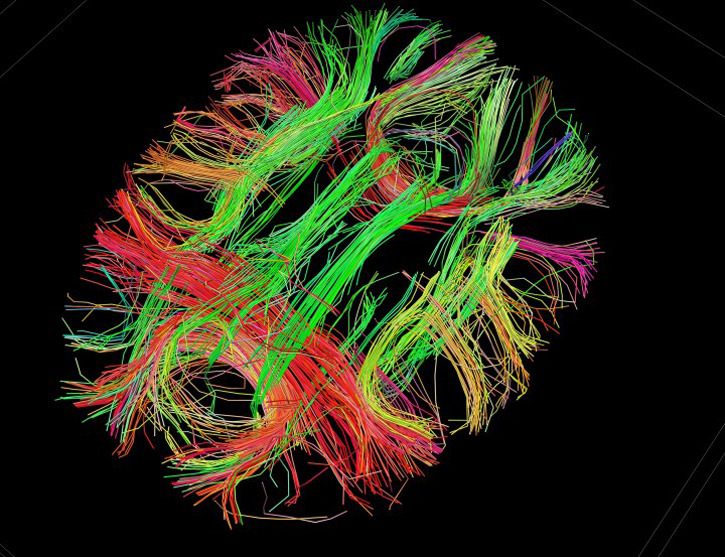

Our thoughts are the result of data traveling along neural pathways. We formulate ideas and reach conclusions based on the way data enters our sensory system, mingles, and gets interpreted.

The Human Connectome Project is all about mapping these pathways to get a better understanding of connectivity in the human brain. It uses advanced MRI technology and techniques.

- Image: Courtesy of the Laboratory of Neuro Imaging and Martinos Center for Biomedical Imaging, Consortium of the Human Connectome Project. White matter fiber architecture of the brain.